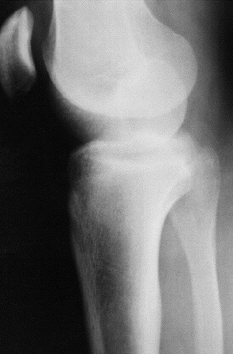

La exploración radiológica simple era sugestiva de un desplazamiento anterolateral de la cabeza del peroné. No se realizó TC (Figs. 1 y 2).

Fig. 2.--Radiografía lateral de la rodilla. Presenta desplazamiento anterior de la extremidad proximal del peroné. Lateral X-ray of the knee. It shows anterior displacement of the end of the fibula.